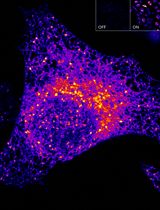

Our real-time kinetic assay using H188 and living cells differs from single-endpoint HTR-FRET assays that monitor levels of cAMP in cell lysates. For example, the LANCE® cAMP assay (Perkin Elmer) uses a Europium-labeled cAMP tracer (FRET donor) in combination with a fluorophore-tagged anti-cAMP antibody (FRET acceptor), both of which are added to a reaction mixture so that the competition of fluorescent cAMP and non-fluorescent cAMP (i.e., endogenous cAMP) for the anti-cAMP binding site on the antibody can be measured. In contrast, H188 is unimolecular in which the cAMP-binding protein Epac1 is flanked by the FRET donor mTurquoise2∆ and the FRET acceptor cp173 Venus-Venus so that a decrease of FRET occurs upon binding cAMP (Klarenbeek et al., 2015). YC3.60 instead uses a Ca2+-binding domain of calmodulin (CaM), and the CaM-binding peptide M13, in combination with the FRET donor ECFP∆11, and the FRET acceptor cp173Venus so that an increase of FRET occurs upon binding Ca2+ (Nagai et al., 2004). Unlike HTR-FRET assays, H188 and YC3.60 allow live-cell real-time determinations of FRET in the kinetic mode.